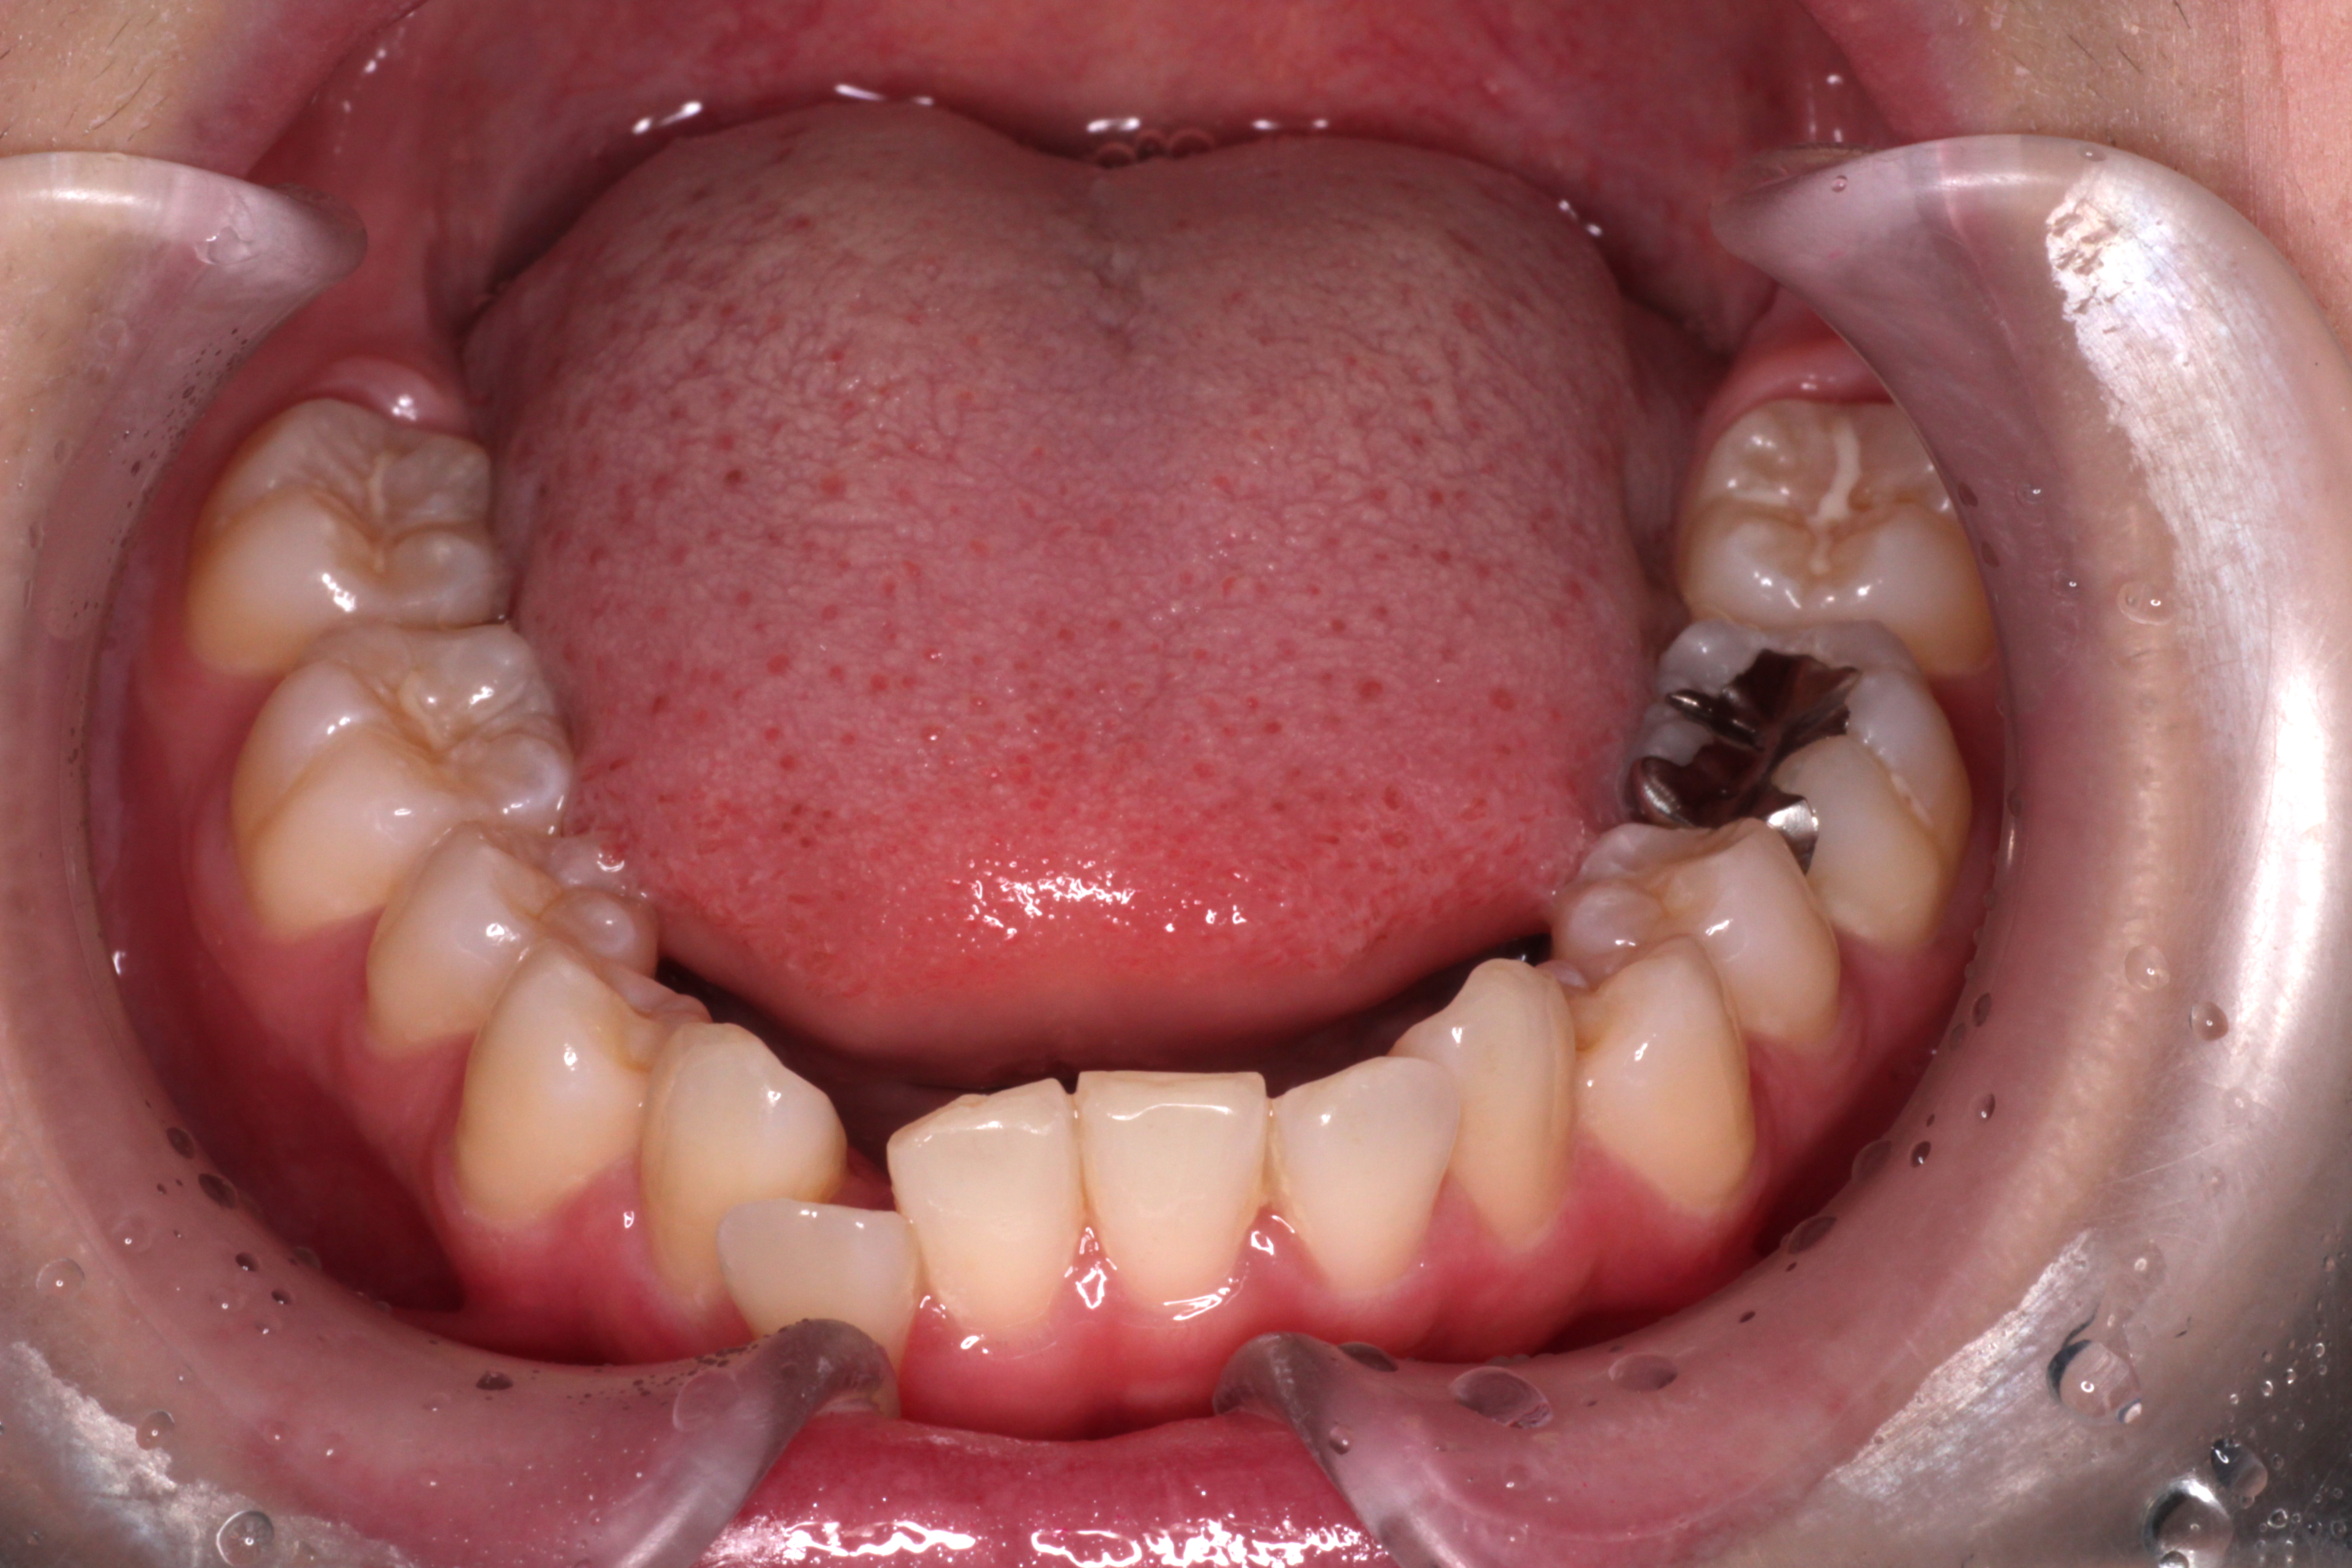

↓お口の中の状態です。

初診時からの変化と治すべきところは

⑴咬み合わせは下の歯が上の歯に隠れていましたが、見えるようになりました。

⑵右下の2番目の歯が歯列の中に納まってきましたが、まだ少しずれています。

⑶右上の2番目の歯は下の歯より前に出ましたが、咬み合わせが浅いです。

ここで新たな問題点が見つかりました。

⑷正中がずれているので、合わせるためにゴムかけをします。

⑴~⑷を改善するためにリファイメントを行います。